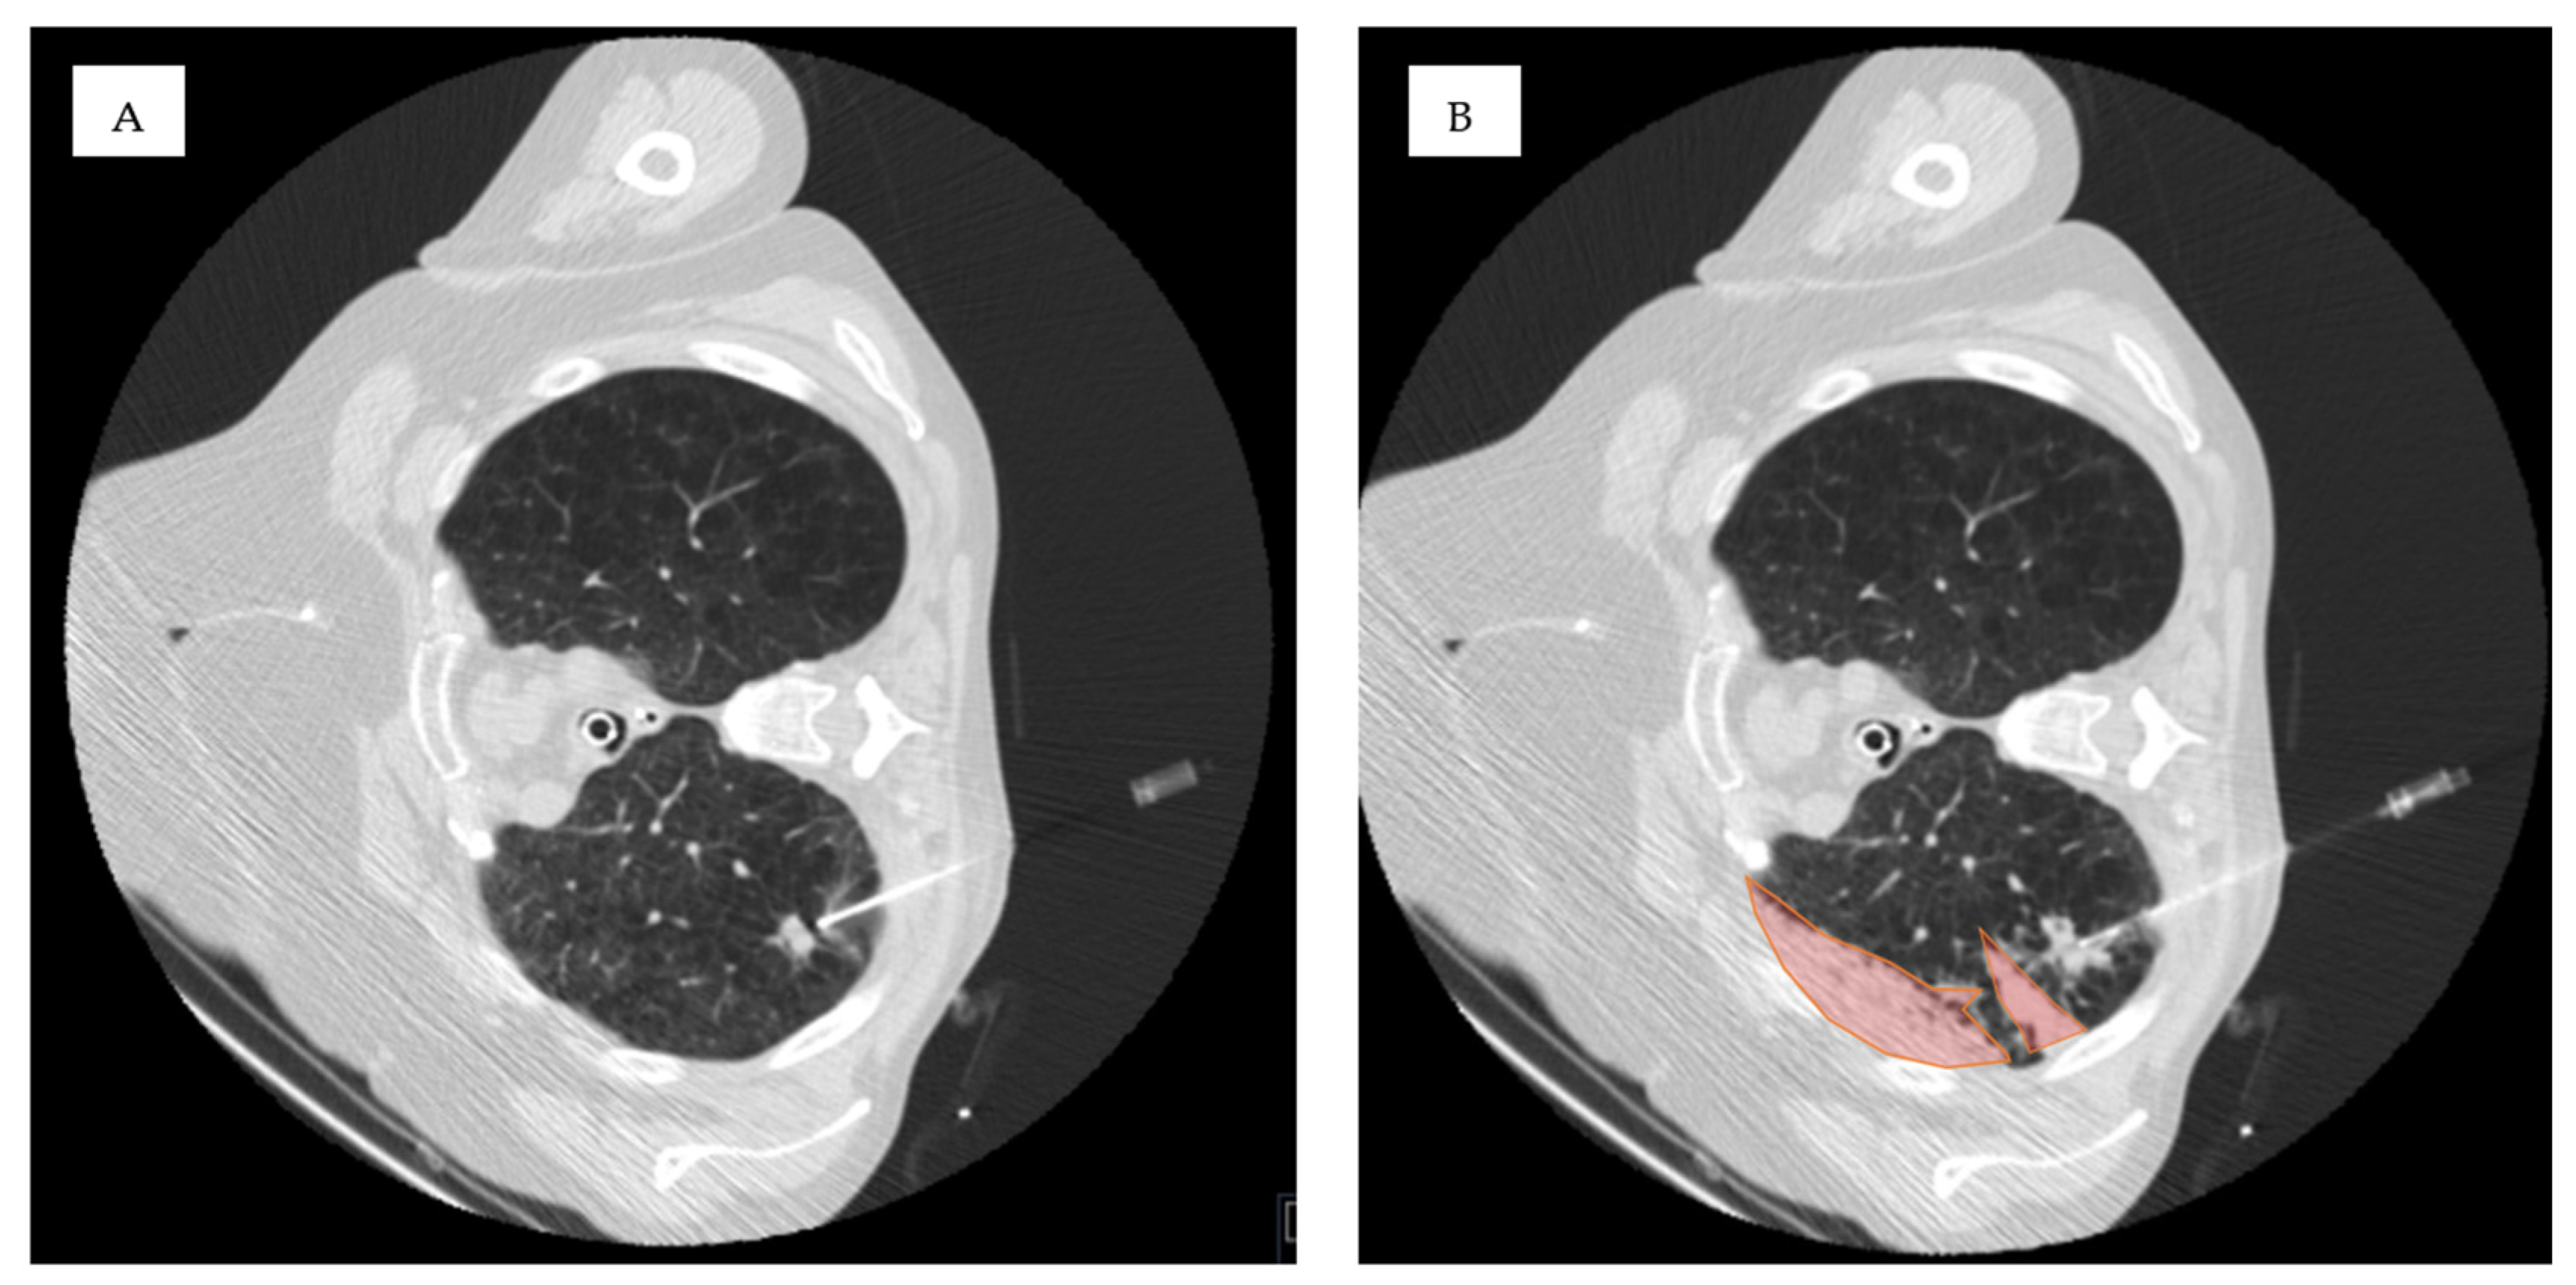

| Lesion location in D area | 53 | 46% | 34 | 40% | 19 | 63% | 0.034 * |

| Ground-glass in the access route | 46 | 40% | 26 | 31% | 20 | 67% | 0.001 * |